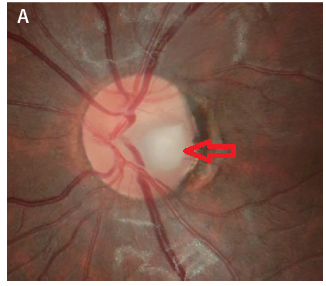

<Disc notching 과의 차이>

시신경유두 패임(Optic disc notching)의 경우, 전반적으로 더 넓고 얕은 패임을 보이며, 유두연으로 확장하는 모습인데,

후천성시신경유두오목의 경우, 국소적으로 좁고 깊은 패임으로, 유두연에 닿고 있는 패임의 양상입니다.